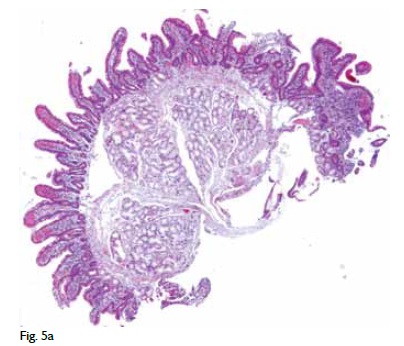

JoL: Nos fragmentos de biopsia obtidos por endoscopia alta não se observaram alterações relevantes. Nos fragmentos obtidos por endoscopia baixa salientava-se a existência de ulceração no cego (Fig. 5A) e alterações inflamatórias com actividade, sem distorção arquitectural, no ascendente, transverso e descendente, com metaplasia de células de Paneth, tal como acontece na doença de Crohn (Fig. 5B).

JoL: Nos fragmentos de biopsia obtidos por endoscopia alta não se observaram alterações relevantes. Nos fragmentos obtidos por endoscopia baixa salientava-se a existência de ulceração no cego (Fig. 5A) e alterações inflamatórias com actividade, sem distorção arquitectural, no ascendente, transverso e descendente, com metaplasia de células de Paneth, tal como acontece na doença de Crohn (Fig. 5B).